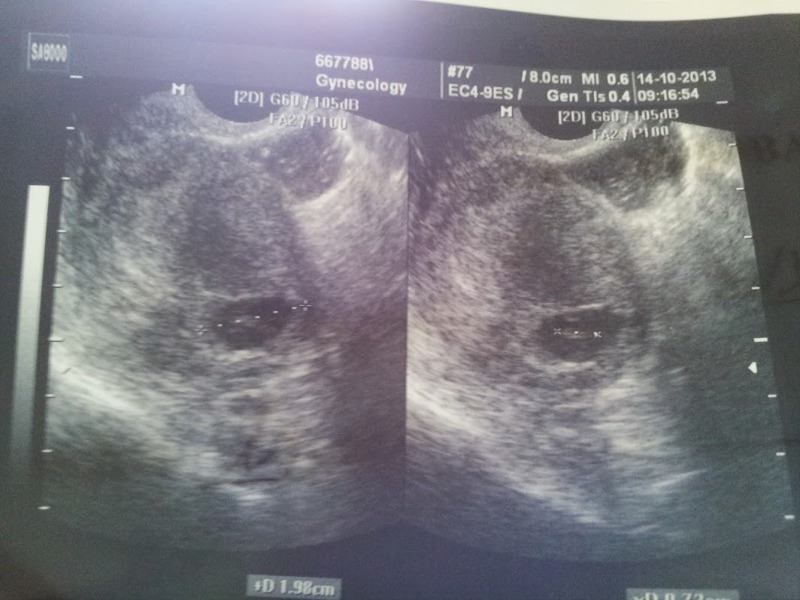

계획하진 않았지만 우리는 이곳에 도착하자마자 둘째를 가지게 되었다. 아직 언어도 제대로 못하고, 무엇하나 스스로 할 수 없는 상황이었다. 그런데, 둘째의 기쁨을 누리기도 잠시... 병원에서 둘째가 위험하단다.

의사의 말이.. 아기의 심장이 멈췄단다.